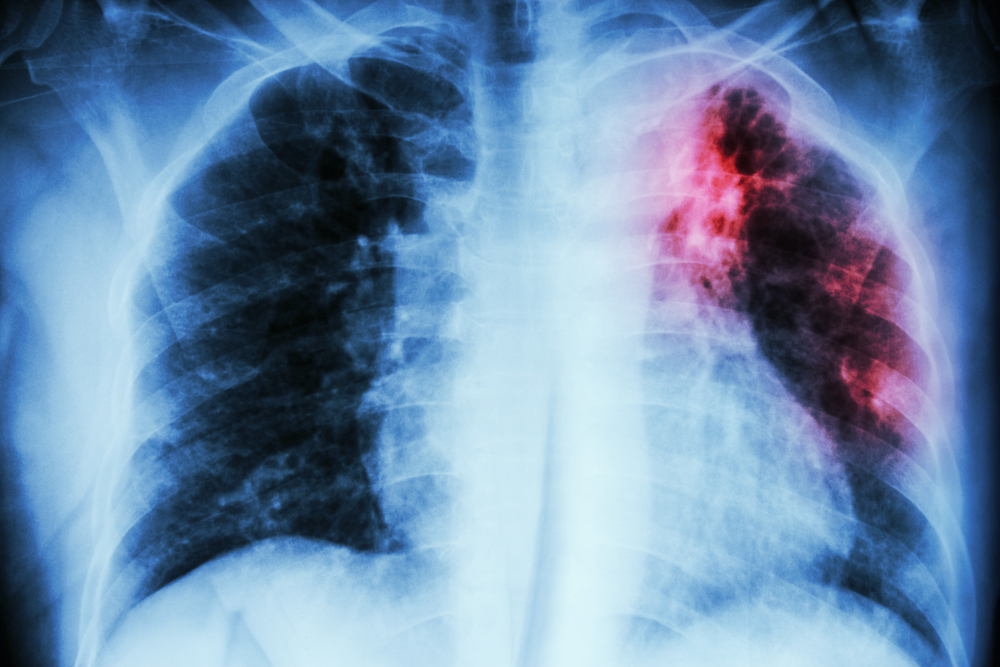

- Krūtinės ląstos rentgenograma

- Kompiuterinė tomografija (KT)